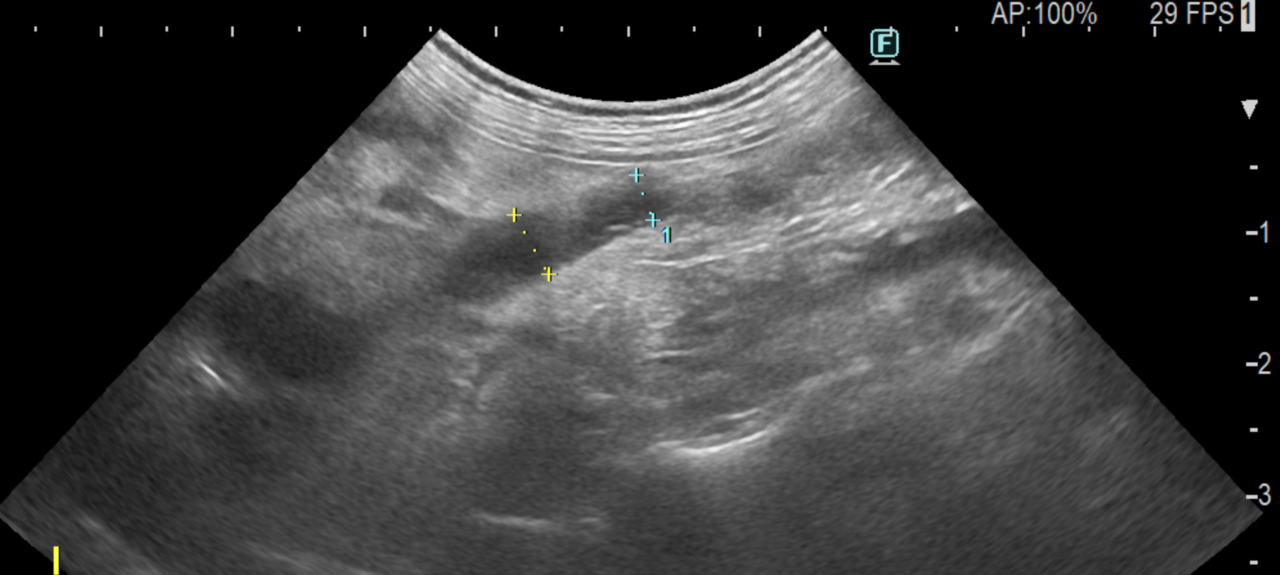

パピヨンの尿管結石症例に対し、外科的に結石摘出を実施した。摘出結石の分析により、成分はシリカ(ケイ酸、SiO₂)と同定された。シリカ結石は犬の尿石症の中でも発生頻度が極めて低いとされ、特に上部尿路(尿管)での発生報告は限られている。また、本結石は溶解療法が無効であり、尿管閉塞を伴う症例では外科的摘出、尿管ステント、SUBシステムなどの介入が必要となる。本症例ではCTやエコーなどの画像診断により尿管閉塞を確認し、腎機能温存を目的として外科的摘出を選択した。術後経過は良好で、現在は再発予防として飲水管理(低ミネラル水)および食事内容の調整を中心に経過観察を行っている。シリカ結石は飲水中の溶存ケイ酸量や生活環境との関連が示唆されており、まれな結石であり、成分分析に基づく原因評価と長期管理戦略が重要であると考えられた。